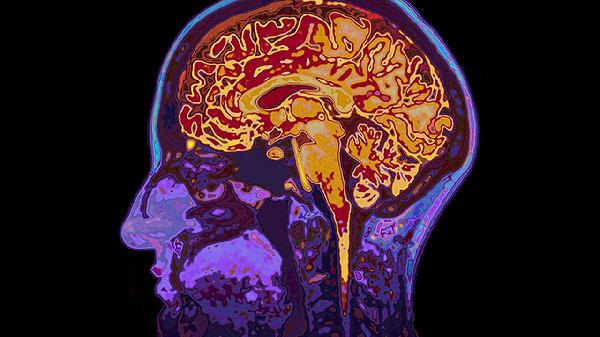

脑血栓片使用期间应注意避免食用辛辣刺激性食物,忌烟酒。服药期间如出现皮肤瘀斑、牙龈出血等异常情况应及时就医。脑血栓患者日常应注意控制血压、血糖、血脂等危险因素,适度运动有助于促进血液循环。饮食上建议低盐低脂,多吃新鲜蔬菜水果。定期复查凝血功能和脑部影像学检查,观察病情变化。